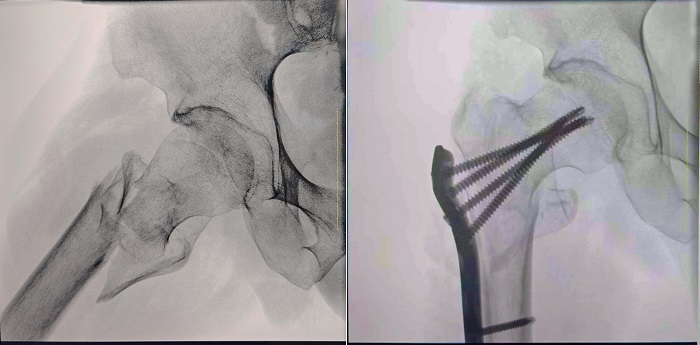

“術(shù)中影像”作為骨科醫(yī)生的“另一雙眼睛”,其圖像的清晰度和成像范圍,對(duì)于醫(yī)生的診療決策有著舉足輕重的影響。普愛醫(yī)療一體式移動(dòng)C型臂卓越的硬件配置和圖像處理性能,提升了術(shù)中影像的清晰度和細(xì)節(jié)展現(xiàn),尤其是針對(duì)骨盆髖臼、長(zhǎng)骨骨折等需要大視野成像的手術(shù),設(shè)備的優(yōu)勢(shì)尤為明顯。以下,以浦北縣中醫(yī)院開展的股骨粗隆骨折病例為例,詳細(xì)闡述普愛醫(yī)療大平板一體式C形臂如何助力醫(yī)生實(shí)現(xiàn)更精準(zhǔn)的診療。

患者:70歲,男

臨床診斷:右股骨粗隆間骨折,伴有下肢位移、外旋

術(shù)式:右股骨粗隆間骨折切開復(fù)位內(nèi)固定術(shù)

一體式移動(dòng)C型臂拍攝的術(shù)前影像

普愛醫(yī)療一體式移動(dòng)C型臂采用30CM×30CM的平板探測(cè)器,能夠幫助醫(yī)生全面觀察患者斷端分離錯(cuò)位情況,確保手術(shù)方案的精準(zhǔn)制定。